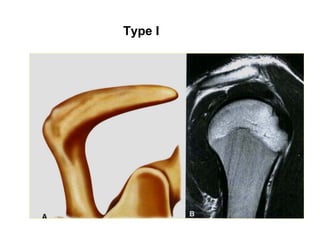

Type I

Type II

Type III

Type IV

Moûm cuøng vai vò trí bình thöôøng